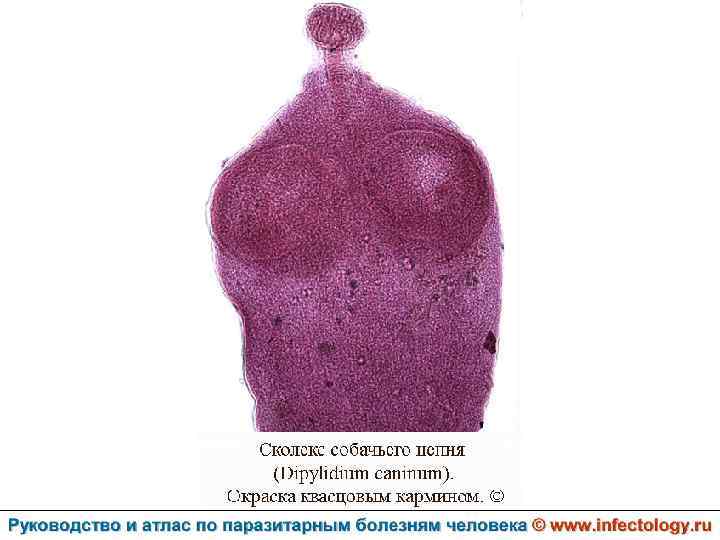

Дипилидиоз (шифр по МКБ 10 – B 71. 1) зоонозный биогельминтоз, характеризующийся аллергизацией организма и нарушением функций пищеварительного тракта.